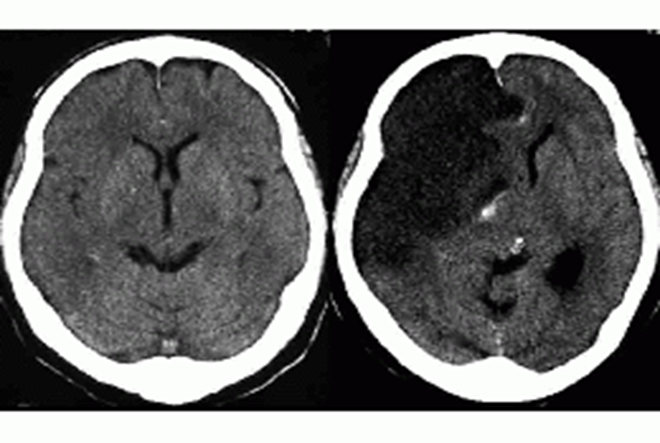

Dense artery sign

Dense basilar artery and middle cerebral arteries on CT

Thrombus in vessel is hyperdense relative to flowing blood